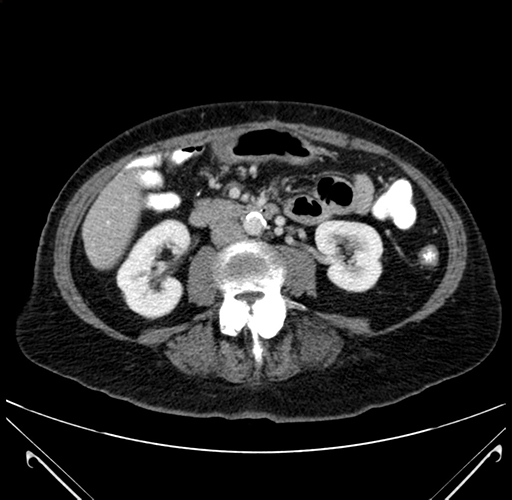

Coronal Venous